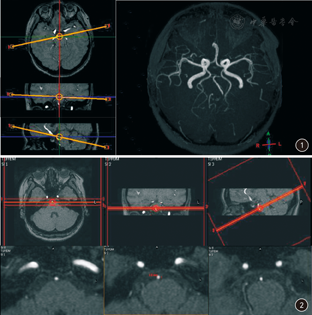

应用荷兰Philips MR仪自带VolumeView软件对MRA资源影像进行多平面重组。在软件处理界面的矢状位上选择基底动脉显示清楚、连续的层面,以此为定位图。分别选择基底动脉近、中、远段的中点3处,截面为圆形或近似圆形,避开有小脑前下动脉、小脑上动脉等大血管分支开口处,以层厚2 mm、间隔1 mm、垂直于基底动脉走行方向进行图像重组(图1)。

每例患者基底动脉取3个截面,每个截面分别测量基底动脉管腔不同方位的两个内径,取平均值;再取3个截面测量数值的平均值,作为该入组者基底动脉直径(图2)。